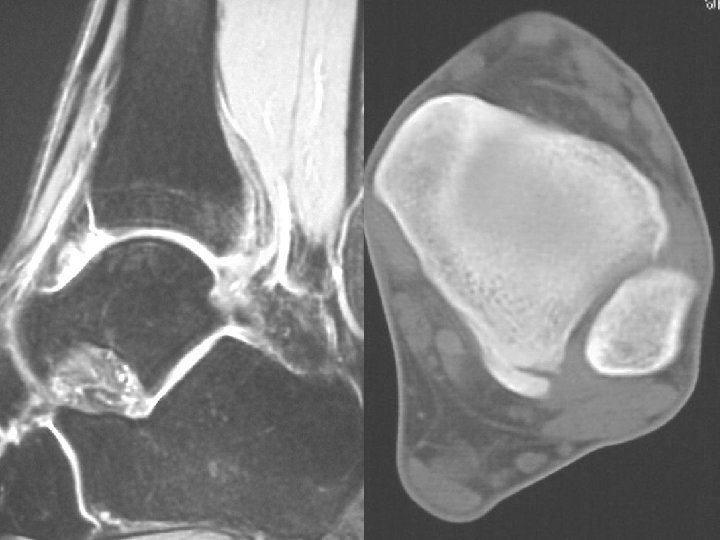

Ossification Traumatic Burns • Commonly elbow • Occurs distal to burn

Burn